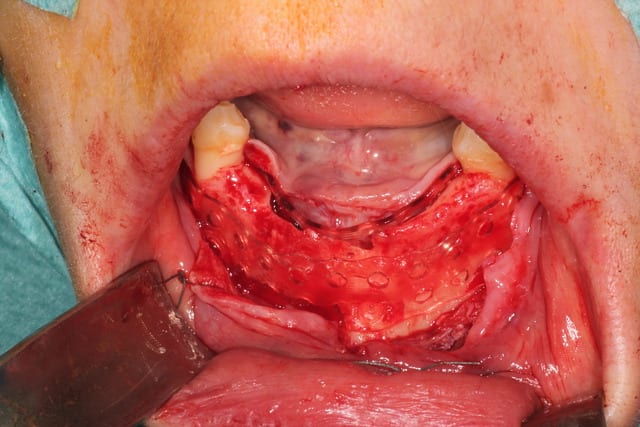

Bon, finalement, j'ai fait comme ça :

Oui, c'est bien en boxtechnique. J'ai fait une formation en avril dernier avec Andrea Menoni , initiateur de la technique en 2008. Je pense poursuivre à parme en octobre.

j'ai donc utilisé comme Maximini du MinerOss cortical-spongieux + autogene + prf + metro.

recouvert de prf, d'une membrane jason pericadium et de prf.

plaque resorb X , 0.8 mm, 11x126 mm : 235 €

5 pins : 350 €

MinerOss : 2.5 +1 cc : 360 €

Jason 4x3 : 180 €

Total : 1120 : oups, devis 1280 ! 3 heures !

Sur la video , il y a les deux techniques pour donner de la flexibilité au lambeau : technique Andréa avec le décolleur en lingual, et Maximini avec le Metzenbaum en vestibulaire.